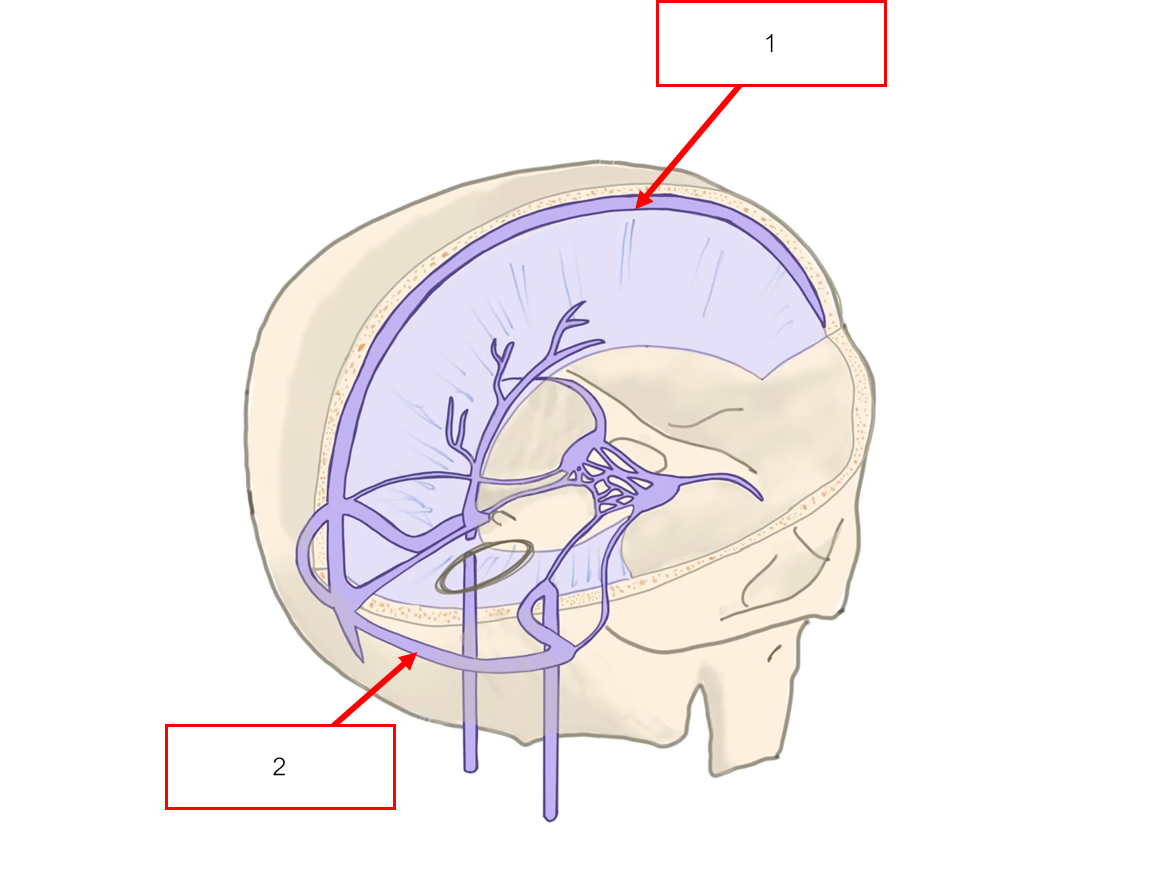

Outer periosteal layer

Dura mater

Subdural space

Arachnoid mater

Subarachnoid space

Pia mater

Cerebral hemisphere

Falx cerebri

Dorsal sagittal sinus

Arachnoid villi

Arachnoid + Pia mater รวมกันเรียกว่า

Leptomeninges

Dura mater แบ่งเป็น 2 ส่วน คือ

Inner meningeal layer